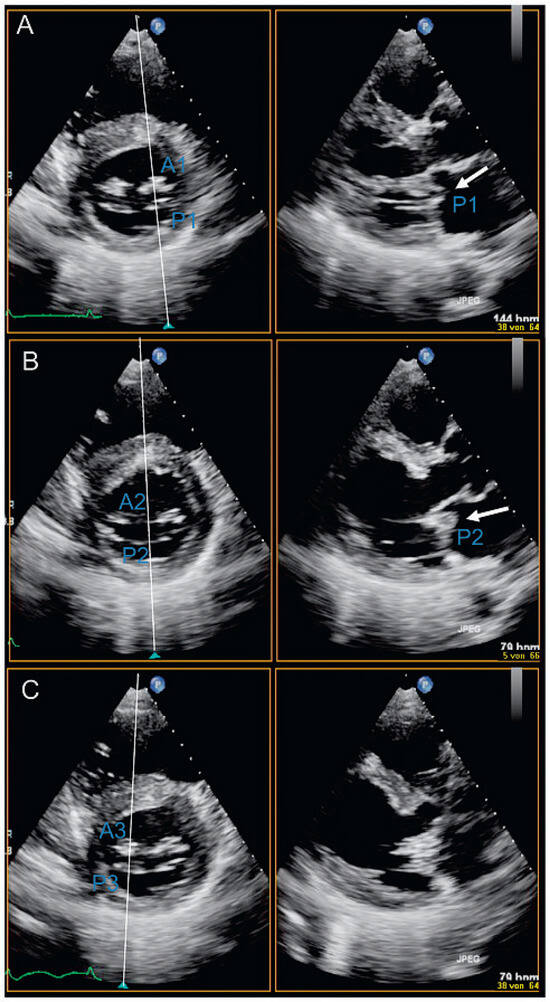

Dreidimensionale Echokardiographie zur Beurteilung der Mitralklappe

Using two-dimensional echocardiography, the complex anatomy of the mitral valve needs mental reconstruction into its three-dimensional shape. The power of both transthoracic and transesophageal three-dimensional echocardiography (3DE) lies in its possibility of showing the complex mitral valve anatomy in one single image, as [...] Read more.

Using two-dimensional echocardiography, the complex anatomy of the mitral valve needs mental reconstruction into its three-dimensional shape. The power of both transthoracic and transesophageal three-dimensional echocardiography (3DE) lies in its possibility of showing the complex mitral valve anatomy in one single image, as opposed to the mental reconstruction based on multiple two-dimensional images and schematic assumptions. Several 3DE modalities are used in daily life, including real time (“live”) modes as wells as postprocessed images. 3DE is of special interest in the evaluation of mitral stenosis, complex mitral valve prolapse and mitral valve prostheses. It has an established role in the perioperative mitral valve assessment during mitral valve surgery as well as during percutaneous mitral valve procedures. Limitations of 3DE are relatively low frame rates, an important learning curve as well as timeconsuming processing. Full article

Show Figures

Figure 1